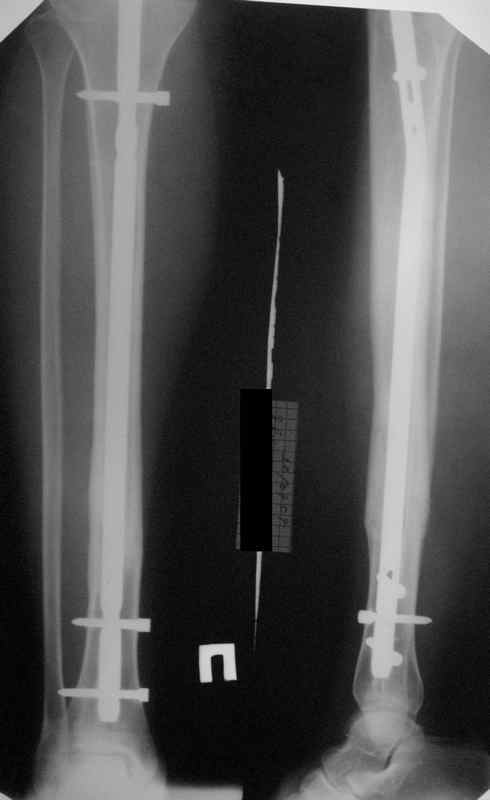

В приложении картинка пациента со сломанным внизу гвоздем. Начал лечение в другом учреждении. Еще и адвокат к тому же.

Динамизировали через 8 недель, а оно поползло больше, чем хотелось бы.